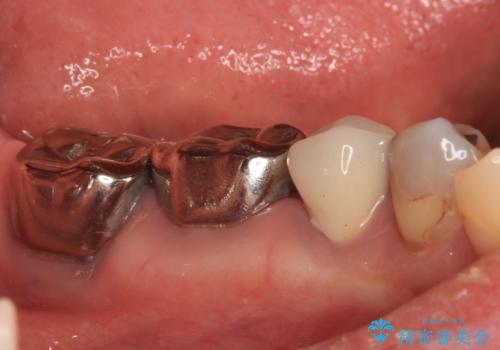

銀歯を外したところ、非常に大きなむし歯が認められましたが、神経組織には及んでおらず、速やかにオールセラミッククラウンによる補綴治療を行いました。